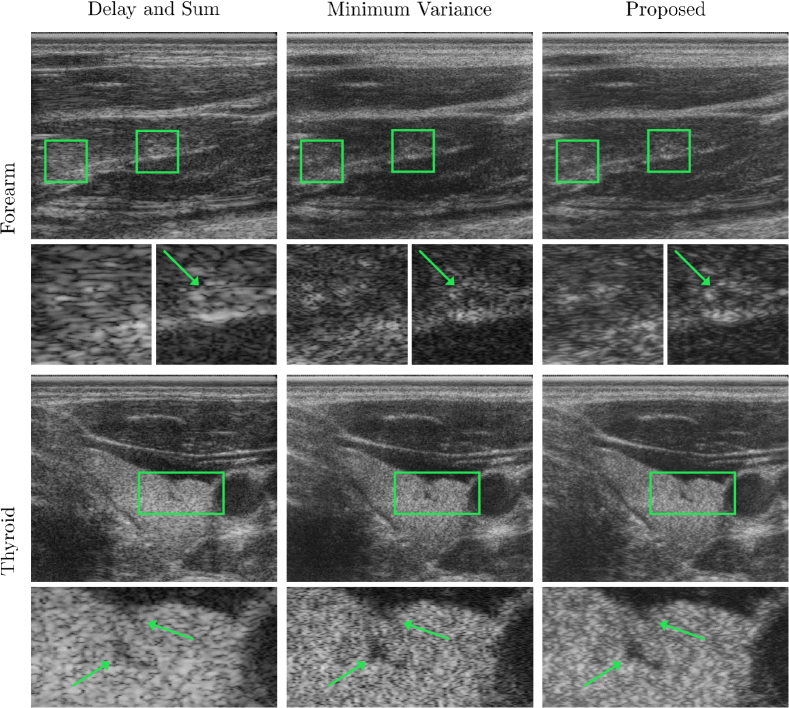

A comparative evaluation of the proposed loss can be found in Table 1. The PSNR-MSSSIM loss performed best w.r.t. both mean and standard deviation of SSIM, exhibiting comparable PSNR. Consequently, we perform inference to generate evaluation images with the PSNR-MSSSIM loss. Figure 2 shows a qualitative comparison between reconstructions with DAS, MV, and our method. In the detail views, arrows point to regions where the reconstruction of fine anatomical structures is compared. The proposed reconstruction displays the least noise contamination around the indicated annular structure (right detail forearm). The same observation can also be made in the global view of the forearm scan. In MV and our method, the border of the thyroid (lower detail images), as well as the vessel contained therein, are depicted more clearly.

Refer to caption

Figure 2: Qualitative evaluation on two anatomies of unseen volunteers. (left) Delay and Sum, (center) Minimum variance, (right) our reconstruction. (top) supinated forearm, interior muscle (Brachioradialis), (bottom) thyroid cross-section.